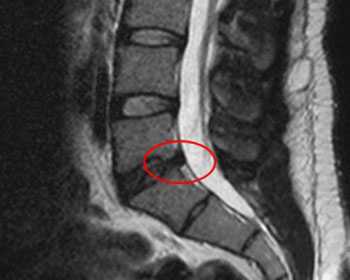

Остеохондроз осложненный грыжеобразованием. Мучительные боли в спине купированы за один сеанс. Неврологические проявления-мурашки по ногам, онемение голени ушли со второй процедуры. Курс - 2 недели.